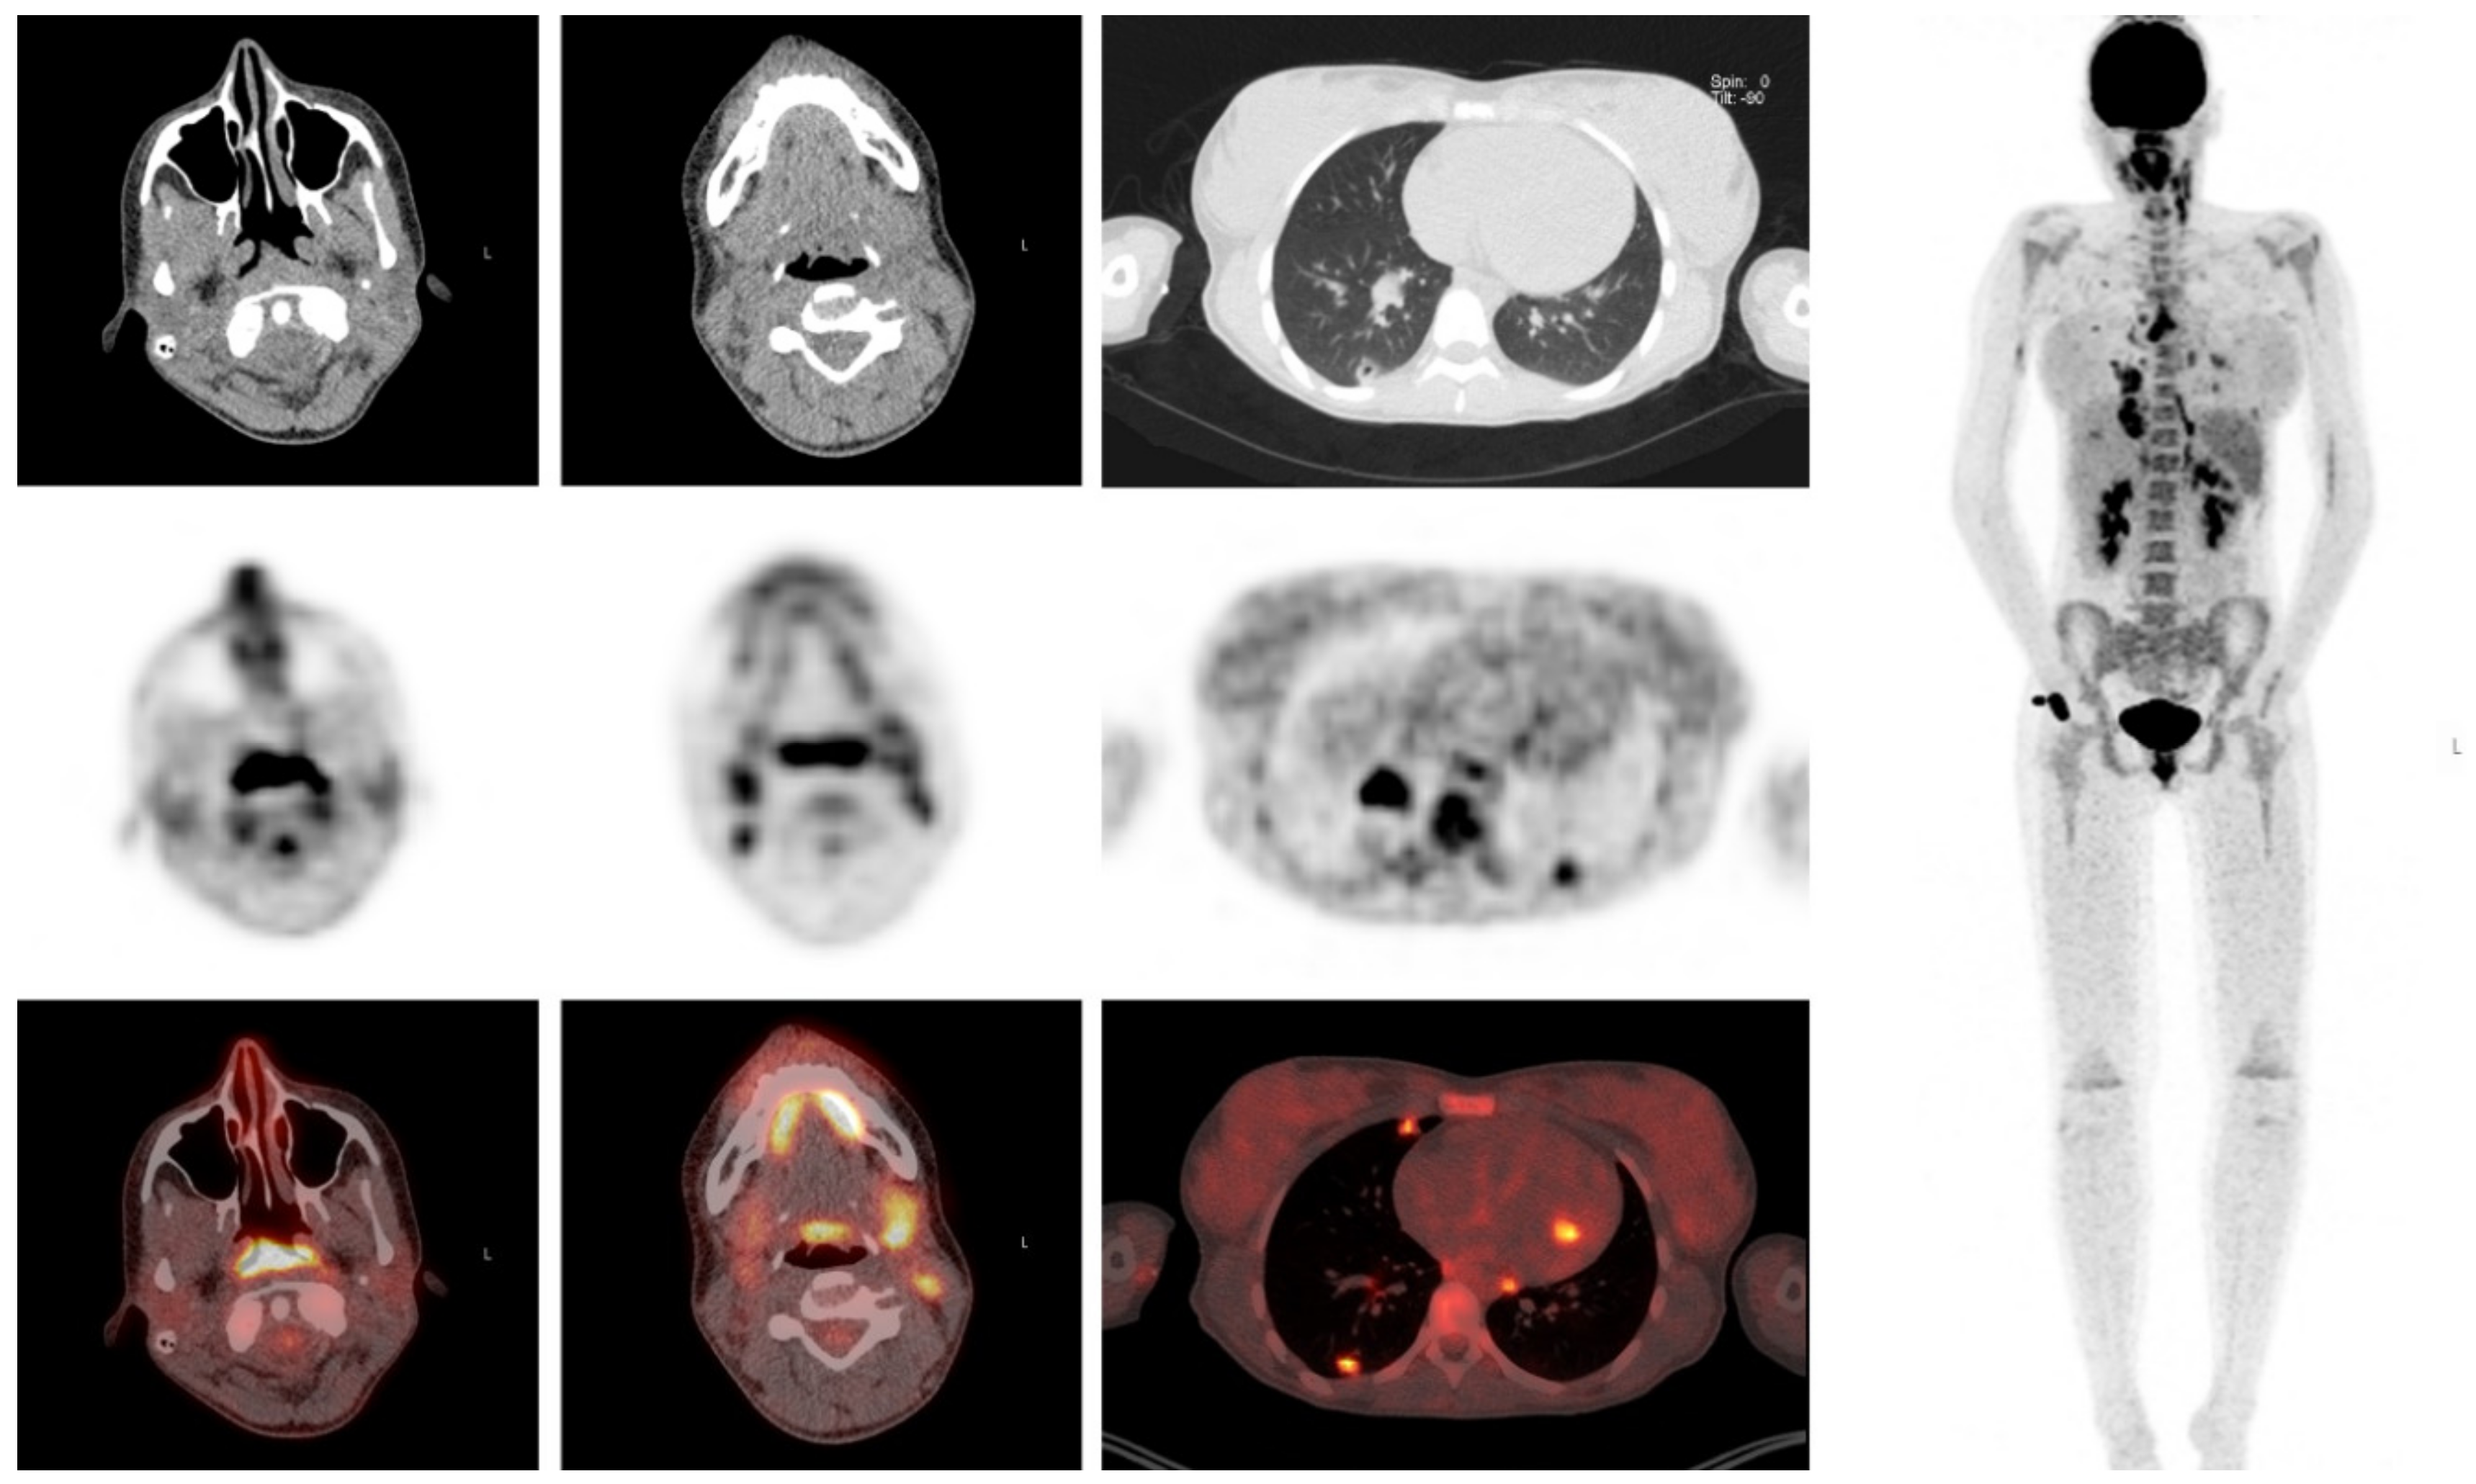

A 16-year-old girl with an episode of sore throat one week earlier, presented with elevated inflammatory markers (maximum CRP 259 mg/L, ESR 60 mm/h), fever, hypotension and right upper abdominal pain radiating to the back. She was treated empirically with intravenous ceftriaxone. Because of persisting abdominal pain, ultrasound, chest X ray, and a diagnostic laparoscopy were performed. The latter because of suspected cholecystitis, which could be excluded. The fever subsided under antibiotic treatment. Because of persisting malaise and a yet unknown diagnosis, a FDG- PET/CT was performed. The differential diagnosis before FDG-PET/CT comprised infectious, autoimmune and oncologic causes. FDG-PET/CT revealed cavitating pulmonary lesions and FDG uptake in lymph nodes in the neck, mediastinum and abdomen and in the tonsils and nasopharyngeal region. FDG-PET/CT findings combined with the history of sore throat guided the diagnosis towards Lemierre syndrome, which was confirmed by ultrasound showing thrombosis of the jugular vein. After establishing the diagnosis and clinical improvement on IV antibiotics, the patient was discharged with oral antibiotics (Figure 6).

Figure 6.

Clinical example 2. Intense FDG-uptake is visualized in the nasopharynx, tonsils, cervical and mediastinal lymph nodes and multiple pulmonary cavitating lung lesions.